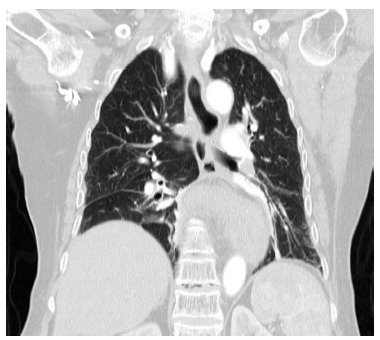

Posteriormente se realizó tomografía de abdomen y tórax con contraste, donde se evidencia hernia de la unión gastroesofágica, fondo y unión antropilórica del estómago hacia el tórax, además de una rotación del estómago en su eje largo, que configura vólvulo gástrico organoaxial (Figura 2).